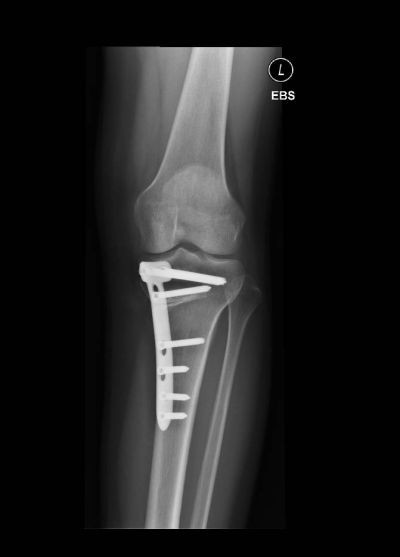

Valgisations­osteotomie

Valgisationsosteotomie